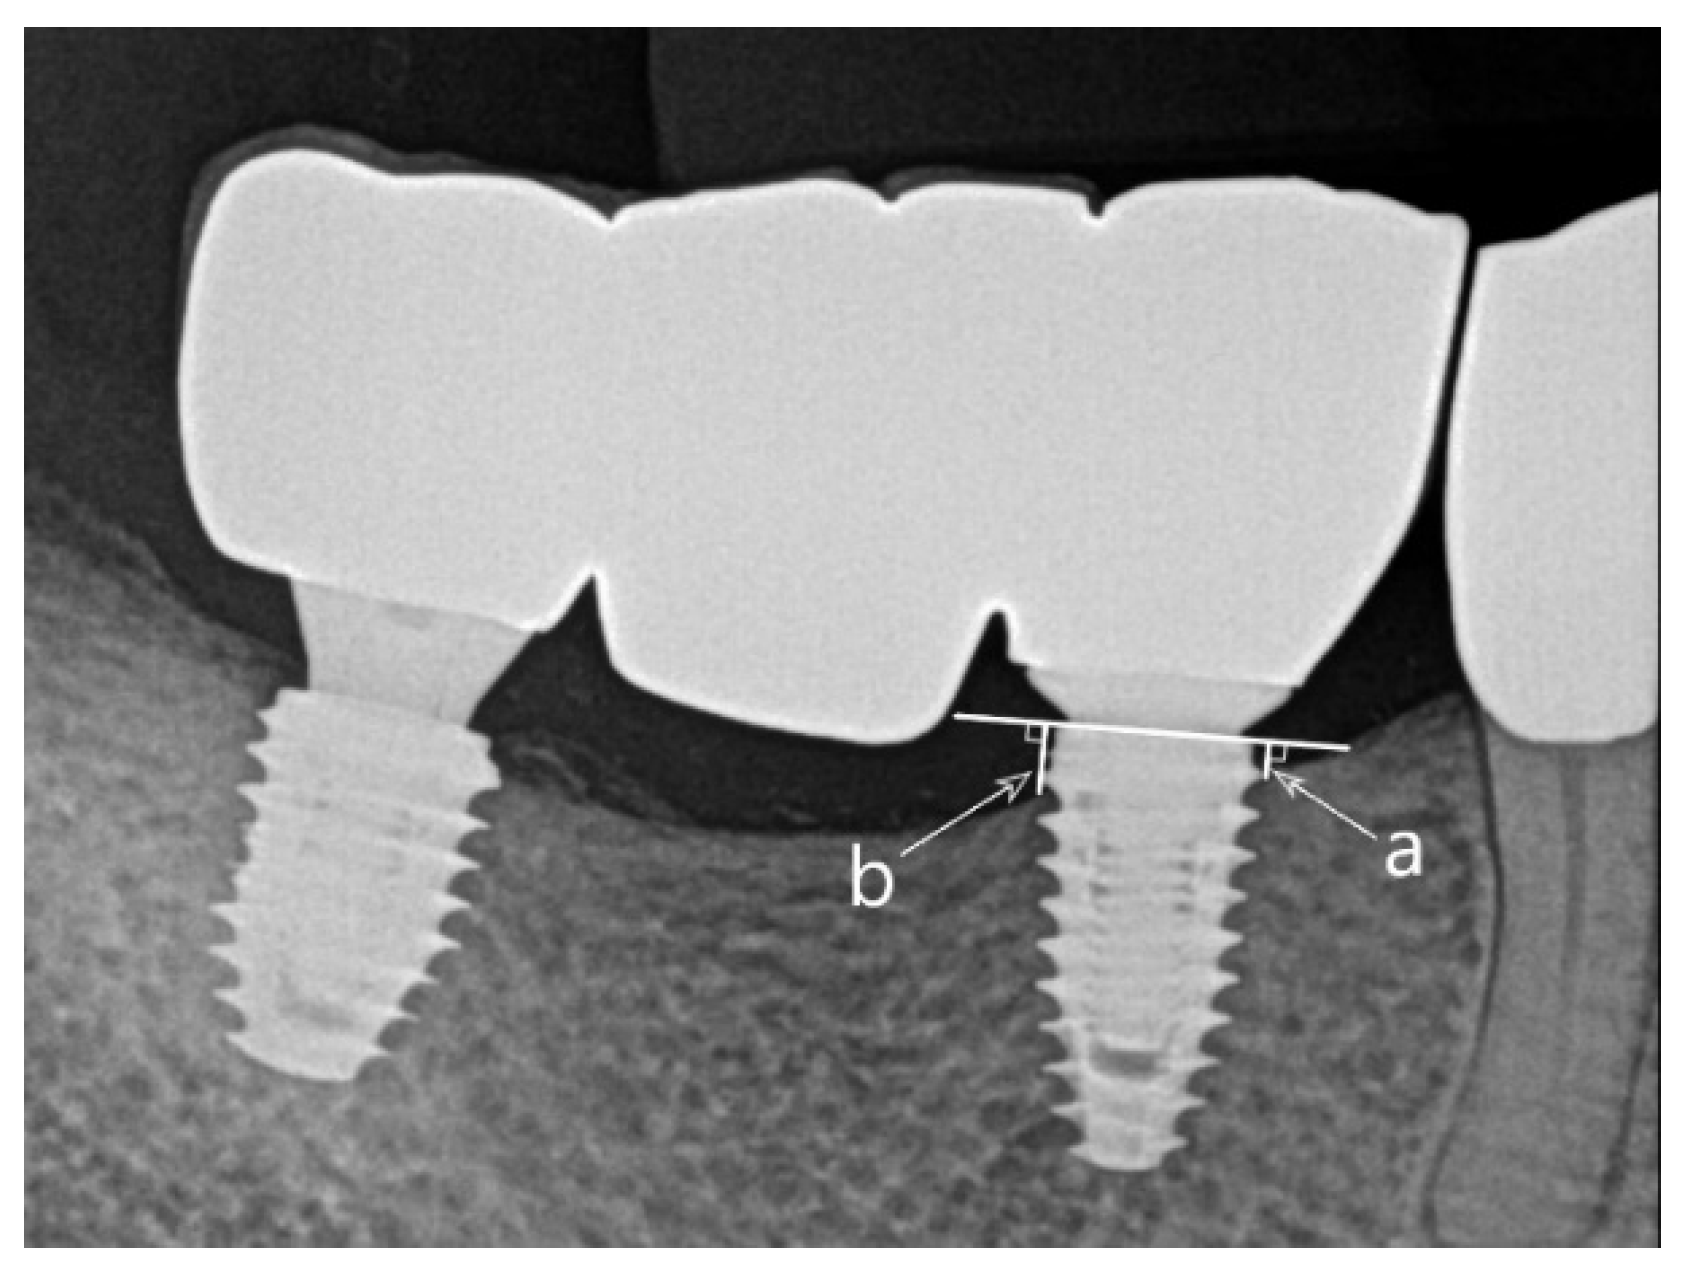

| Marginal bone loss (mm), mean ± SD | Survival rate (%) | Success rate (%) | Follow-up period after prosthesis completion (mo), mean ± SD | |||

|---|---|---|---|---|---|---|

| 1 year | Final | |||||

| All (n=55) | -0.18 ± 0.45 | -0.37 ± 0.70 | 96.4 | 89.1 | 67.3 ± 10.3 | |